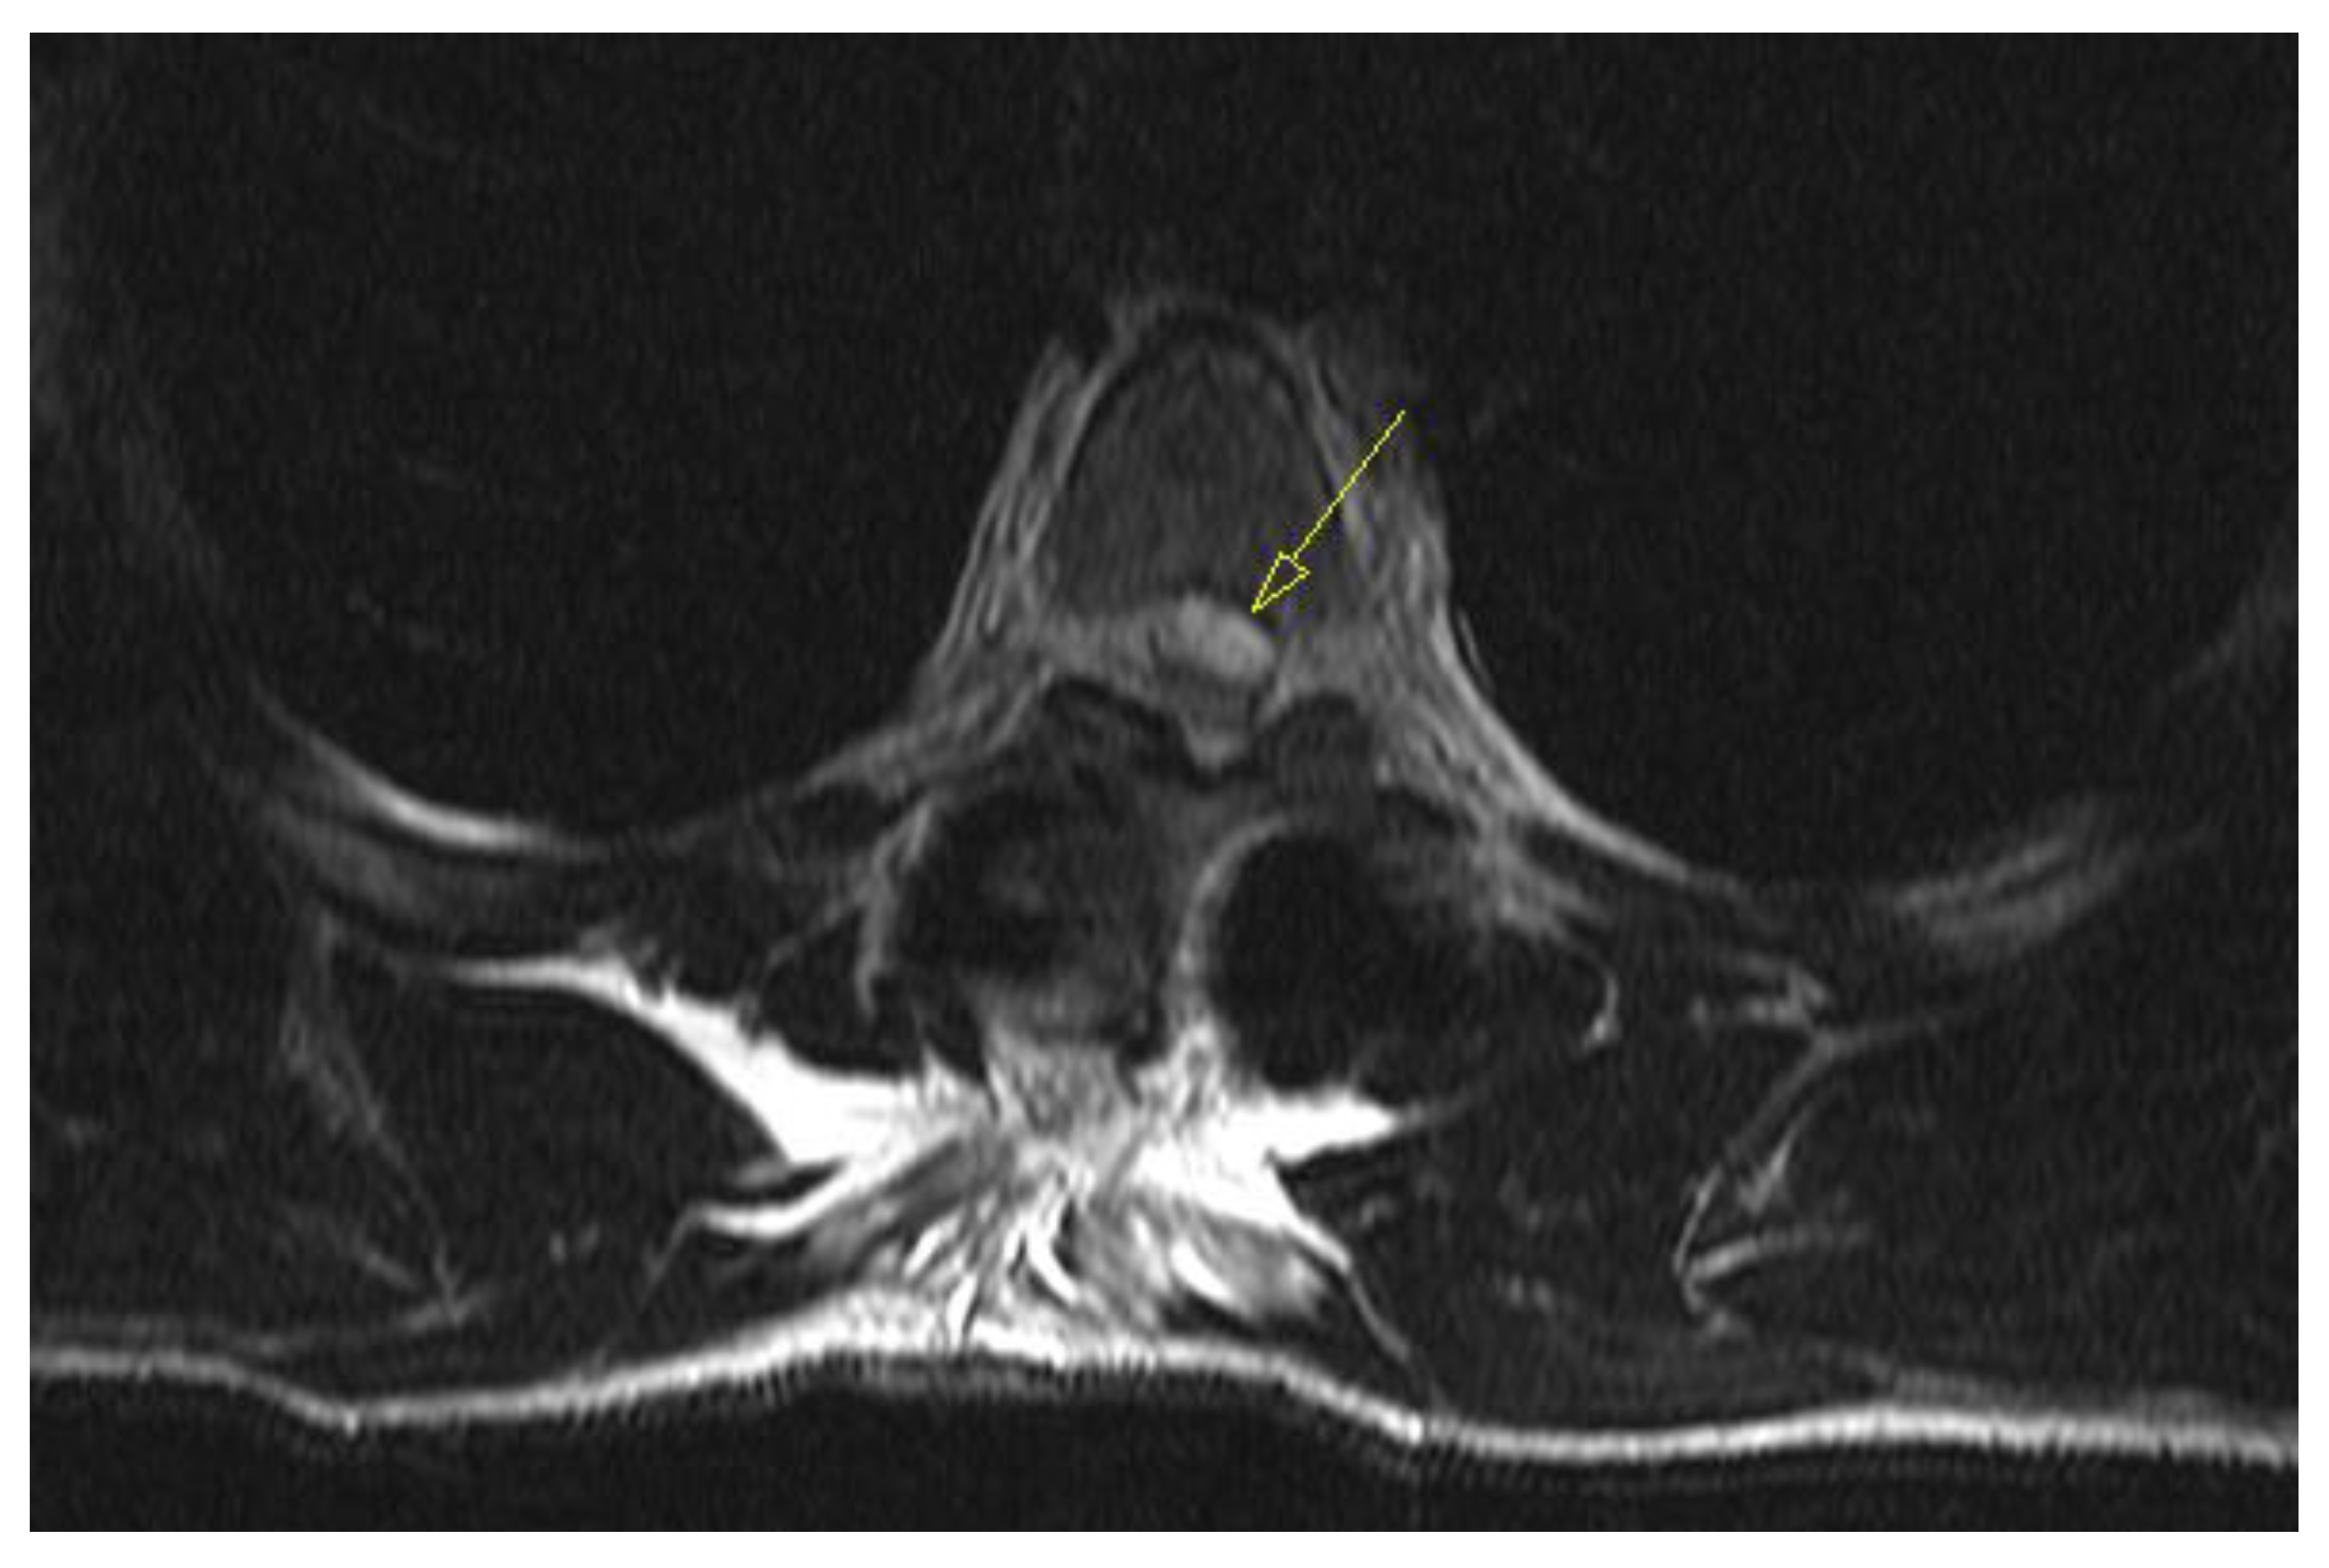

On awakening from general anesthesia, the initial postoperative neurological state was without any impairment, and he was able to urinate spontaneously. Approximately 45 minutes after surgery, he began to develop signs of hypesthesia in the lower extremities, weakness in the legs, an unsettling sensation in the abdomen, and was covered with cold sweat. Due to neurological worsening, an emergency MRI of the thoracic spine was performed, which revealed a hyperacute epidural hematoma that developed at the level of the Th6 fracture and spread cranially to Th4 as shown in Figure 3. The width was measured at 7mm and compressed the spinal cord against the laminae as shown in Figure 4. Most likely the bleeding occurred from the fracture itself.

Figure 4. Emergency T2 weighted MRI image, axial view at the Th5 level, revealing hyperacute hematoma development anterior to the spinal cord and causing significant dorsal displacement and compression.